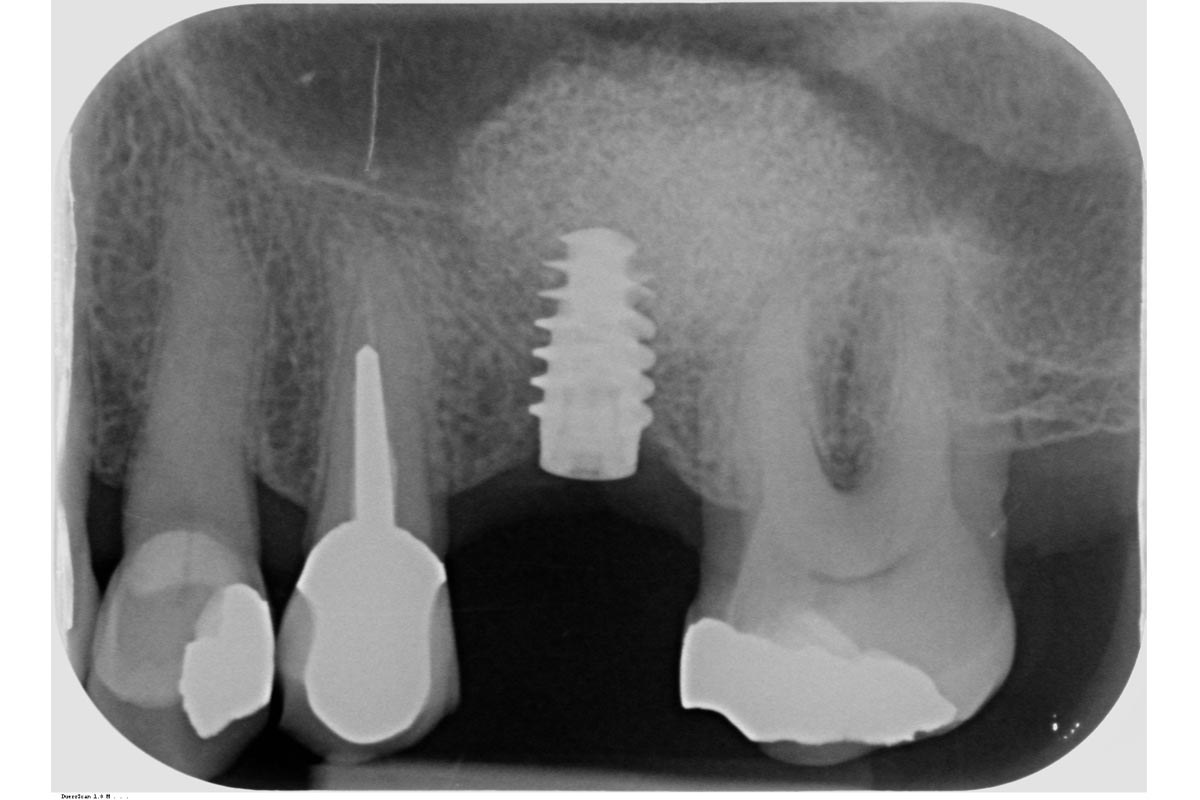

29/35 - X-ray control after the second stageMaxillary sinus cyst removal using the Crocodile Technique and subsequent lateral sinus lift - Dres. C. Scognamiglio and A. Perucchi